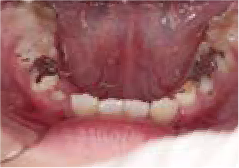

口が閉じない

指しゃぶりのクセがあり、お口を閉じることができません

Aさん (矯正開始時:7歳)

Before

After

舌の位置が低く、上あごの天井が高くて狭い状態でした。鼻がつまりやすく、口をポカンと開けながら呼吸をしていることが確認されました。

治療を終えて

現在まだ治療継続中ですが、装置によって上あごを広げ、下の歯の位置を整える治療中です。お口のトレーニングにより鼻通りがよくなり、鼻呼吸が改善され舌の位置も正しくなりました。指しゃぶりのクセもなくなりました。

主訴・治療内容 指しゃぶりのクセがあり前歯が傾いていることから、お口を閉じることができないというお悩みで来院されました。

治療期間 1年

費用 495,000円(税込)